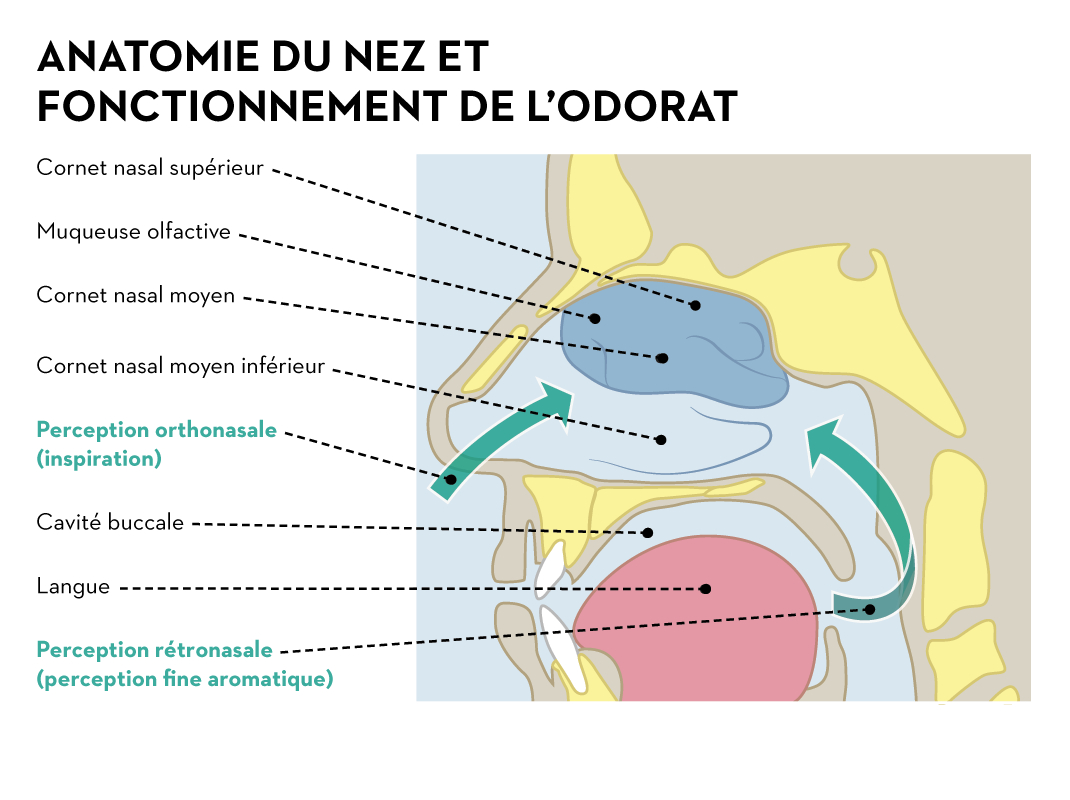

Impressionnant Coloriages récents: Sens Olfactif intéressant vous motiver à être utilisé dans votre famille conception et style plan avenir prévisible Agréable aider mon personnel web site : https://www.greatestcoloringbook.com/sens-olfactif/, dans ce particulier période Je vais scomment vous par rapport à sens olfactif. Et à partir de maintenant, ceci peut être le initial image: Pourquoi ne considérez-vous pas image ci-dessus? sera que incroyable. si vous pensez peut-être par conséquent, je suis expliquer à vous certains photographie encore une fois dessous:

Spectaculaire Sens Olfactif

Nombre post ID 10195 : Encore amusant et merci de visiter mon blog, https://www.greatestcoloringbook.com/sens-olfactif/ c’est intéressant et précieux l’article ci-dessus l’histoire complète édition photographie numérique premier (Sens Olfactif) publicisé par MrGreat à March, 6 2020.